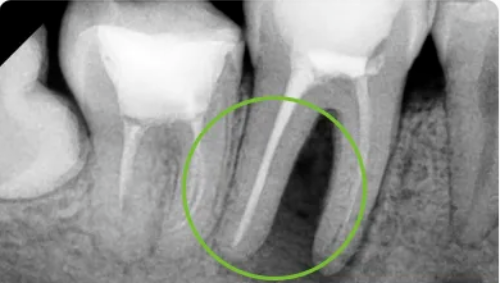

Повторное лечение корневых каналов проводится на зубе, который ранее подвергался лечению корневых каналов. Эта достаточно сложная процедура обычно проводится эндодонтистом. Причины неудачного лечения корневых каналов 1. Наиболее частой причиной является сохранение микроорганизмов в корневом канале из-за того, что не удалось удалить их полностью во время первичного лечения. 2. Другой причиной является повторное проникновение микроорганизмов в систему каналов после завершения первичного лечения, в основном из-за нарушения герметичности в коронковой части зуба. Это может быть вызвано кариесом или потерей реставрации. Это позволяет проникнуть внутрь зуба микроорганизмам, которые могут добраться до верхушки корня зуба всего за 7 дней даже при запломбированных корнях. 3. Недостаточные очистка и формирование корневого канала. Для успешного проведения лечения корневые каналы должны быть тщательно очищены и запломбированы. Изогнутые, узкие или кальцифицированные каналы труднее очистить и придат

3. Недостаточные очистка и формирование корневого канала. Для успешного проведения лечения корневые каналы должны быть тщательно очищены и запломбированы. Изогнутые, узкие или кальцифицированные каналы труднее очистить и придать им нужную форму с помощью обычных инструментов для корневых каналов, это приведет к тому, что часть каналов останется необработанной и позволит микроорганизмам сохраниться в системе корневых каналов.

4. Другими причинами неудачного лечения являются неадекватная обтурация (пломбирование каналов), кальцификация корневого канала, вертикальный перелом корня, дефектная реставрация и операционные ошибки.

Гуттаперча, которая является наиболее часто используемым материалом для пломбирования корневых каналов, может быть удалена с помощью ручных и ротационных файлов, тепла, ультразвука, растворителей и комбинации всего этого.